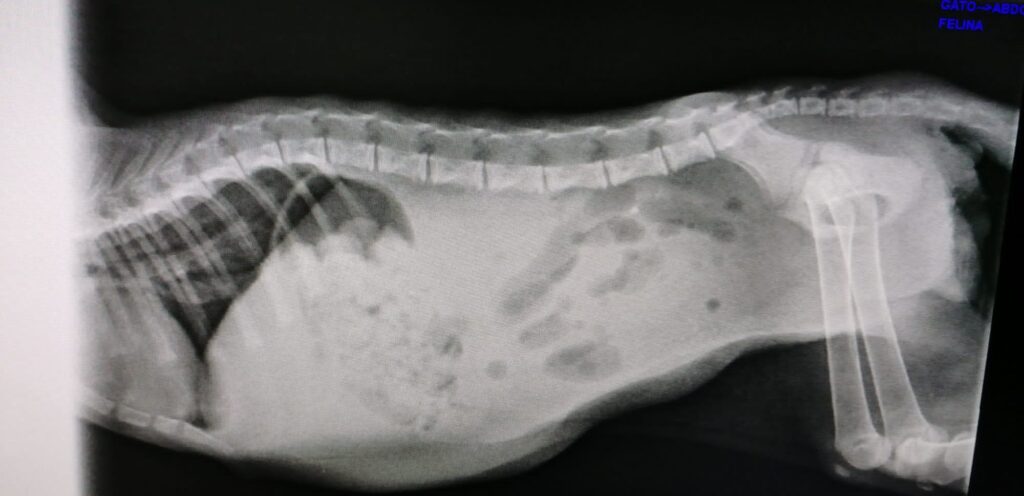

Las pruebas han dado negativo a pif, paleuncopenia y coronavirus. Y el cultivo ha dado negativo a hongos y parásitos en las heces.

Él aún sigue ingresado y lo estará algunos días más, hasta que se estabilice totalmente y no corra ningún peligro.